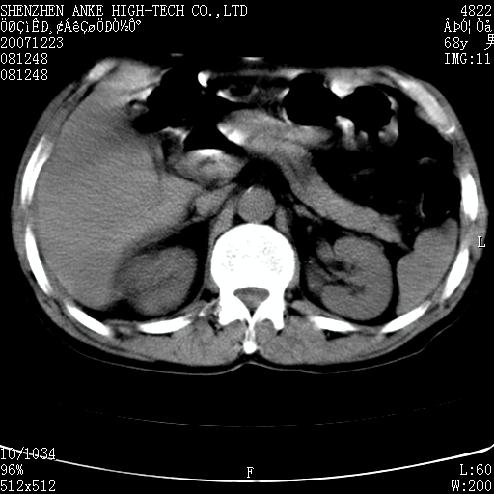

患者:男,63岁,2年前胆囊切除术后,现右上腹部剧烈疼痛近2天.

有无外伤史?右肾包膜下血肿可疑。

主要是问右肾有没有问题?患者无明显外伤史.

未见异常,病人差闭气,伪影较多.

肠管积气明显.

肠道准备不好,干扰影大。

肠道气体伪影干扰太大了,应该是干扰所致,未见明显异常。

肠道准备不好,胃底后壁显示不清,右肾改变考虑为伪影。

上腹部ct平扫未见明显异常。(肠道气体较多,患者呼吸了)